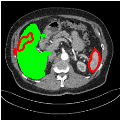

To test the generalizability of SAM-Mix, we validate it on a cross-domain dataset (TotalSegmentator). As reported in Table 2, the segmentation performance of SAM-Mix on the cross-domain task is as promising as the in-domain results. Despite the data shifts, from LiTS to TotalSegmentator, SAM-Mix outperforms all of the baseline models in terms of generalizability, by significant margins. SAM-Mix-50 achieves a Dice score improvement of 25.4%, and a lower Hausdorff distance by 62.26% compared to the best-performing full-supervised U-Net model. These results further validate the few-shot capabilities and establish our SAM-Mix as a well-generalized tool for medical image segmentation.